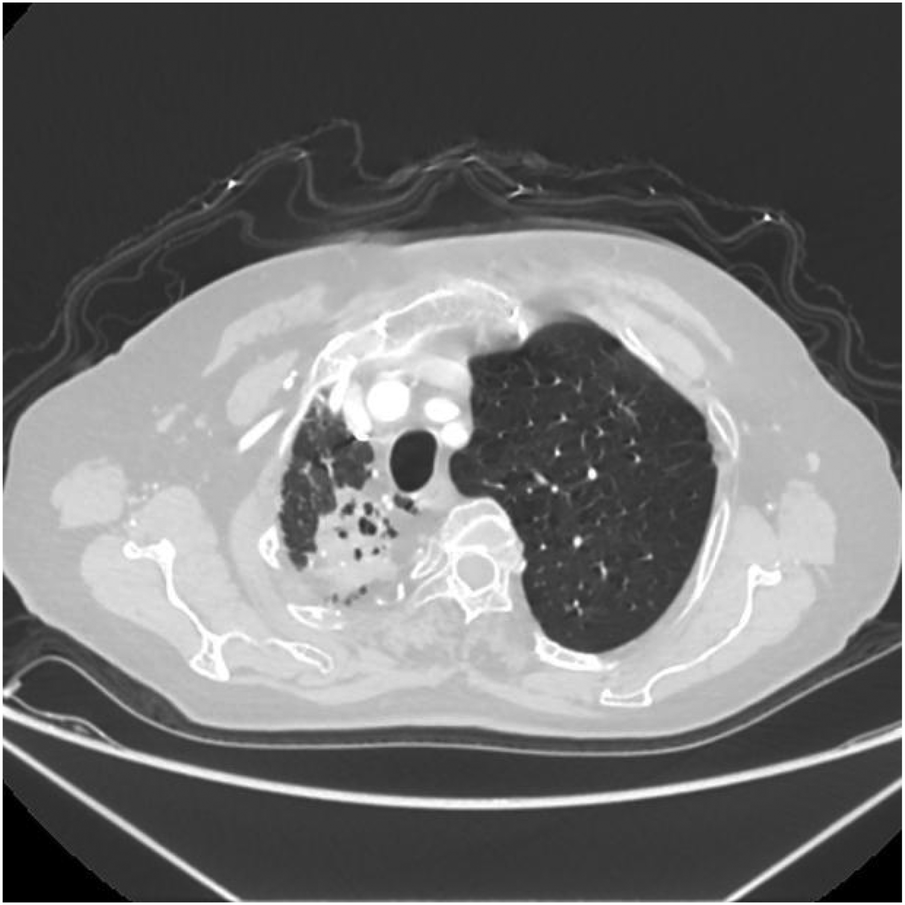

Figure 9

Axial image shows narrowing of the right thoracic cage, reduction in right lung volume, and patchy increased density shadows in the upper lobe of the right lung.

Figure 10

Axial image shows bronchiectasis in the right lung with surrounding inflammation and linear opacities, thickening of the right pleura, and rightward shift of the trachea and mediastinum.

Figure 11

Axial image shows partial bronchiectasis in the right lung, partial inflammation and linear opacities in the right lung, thickening of the right pleura, and rightward shift of the trachea and mediastinum.

Thoracoabdominal aortic CTA and chest CT findings are illustrated in Figures 1–14. There was no evidence of aortic dissection. The right pulmonary artery was absent distal to approximately 3 cm from the bifurcation, with a smooth and rounded defect margin. The main pulmonary artery and its major branches showed no abnormal densities. No right pulmonary artery branches were observed in the right lung. Multiple tortuous arterial branches from the right subclavian artery, descending aorta, and right renal artery supplied the right lung. The right hemithorax was smaller, with localized pleural thickening and adhesions bilaterally. Multiple bronchiectasis with thickened walls and patchy, nodular, and linear opacities encircled the right lung. Increased translucency and several hyperlucent regions were visible in the left lung. CT imaging findings demonstrated: 1. Congenital absence of the right pulmonary artery (RPA), with the right lung supplied by collateral circulation originating from the right subclavian artery, right intercostal arteries, and the right renal artery. 2. Right pulmonary hypoplasia, bronchiectasis of the right lung, accompanied by infection and partial consolidation in the right upper lobe, compensatory hyperinflation of the left lung, and multiple bullae in the left lung. 3. Bilateral localized pleural thickening and adhesions. 4. Osteoporosis and mild flattening of the T6 vertebra and compression fractures of T11 and T12.